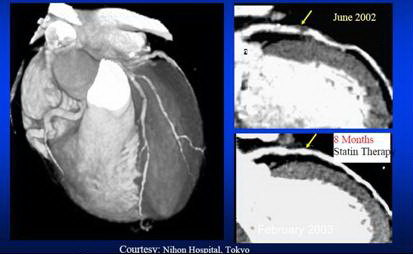

Phương pháp

chụp cắt lớp nhiều mặt cắt (CT multiple slides)

thế hệ mới có thể giúp đánh giá được hệ thống động mạch vành

đoạn gần, đặc biệt là mức độ vôi hóa động mạch vành mà không phải can

thiệp xâm

nhập (chụp ĐMV). (hình 2).

tm_2.jpg

Hình  2: chụp cắt lớp nhiều mặt cắt động mạch

vành trước và sau điều trị